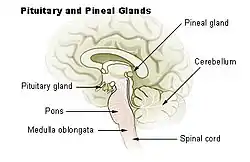

Location of the pituitary gland in the human brain

Location of the pituitary gland in the human brain Pituitary and pineal glands